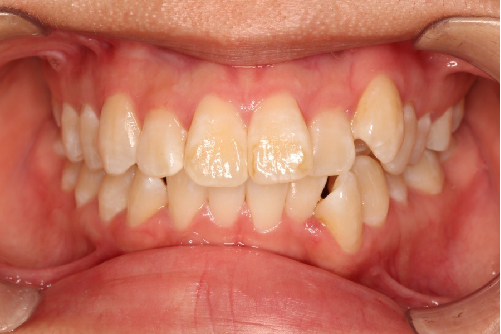

• 磨牙,尖牙I类关系,中线齐

• 上下牙列中度拥挤

• 上下前牙唇倾

IntraoralExamination(2016-08.31,Wu)

1.外观(正面观)面下1/3稍长,开唇露齿,颏部肌肉紧张,露龈笑2外观(侧面观)骨性类高角,凸面型,下颌后缩3上牙列前突,下前牙唇倾度过大4上下牙列中度拥挤

▶凸面型▶开唇露齿,露龈笑▶骨性Ⅱ类,下颌后缩,高角▶Angle I类错𬌗▶上下牙列中度拥挤